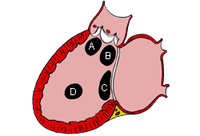

Subtipos dos defeitos do septo ventricular: (A) saída; (B) perimembranoso; (c) entrada; (D) muscular

Mayo Clinic Foundation